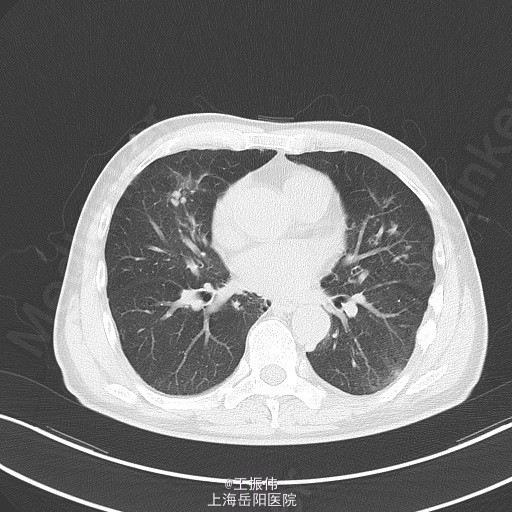

主诉、病史:老年男性,咳嗽咳痰15天,患者15日前因受凉后出现咳嗽,咳黄脓痰,自觉有发热,未测体温,6月25日至我院查血常规:白细胞:7.7*10^9/L,血红蛋白:106g/L,血小板:149*10^9/L,中性粒细胞:68.7,胸部CT:右肺上叶占位灶,两肺小结节灶,纵膈淋巴结增大,左肺下叶、右肺中叶炎症;两肺气肿伴肺大泡。自服止咳中成药(具体不详)后无明显好转。6月27日至地段医院就诊,予头孢羟氨苄片、金荞麦片、强力枇杷露,未见明显好转。

气管居中,颈静脉正常,胸廓两侧对称,无桶状胸,呼吸运动两侧对称,呼吸频率20次/分,肋间隙正常,无胸膜摩擦感。两肺叩诊清音,右肺可闻及湿性啰音,胸部CT:右肺上叶占位灶,两肺小结节灶,纵膈淋巴结增大,左肺下叶、右肺中叶炎症;两肺气肿伴肺大泡。组织病理【z155818】:灰白组织2粒,直径0.1cm。诊断:(左肺下叶开口)肉芽肿性炎,结核可能,请临床做相关病原体检测。支气管镜痰涂片:找到抗酸杆菌。